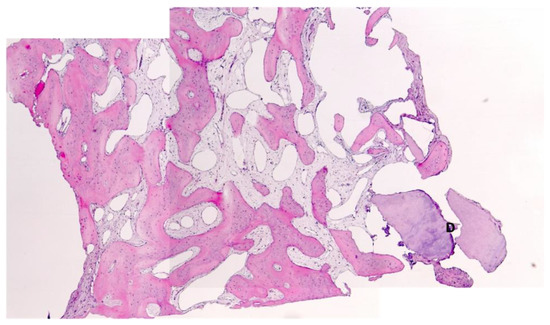

Histological Analysis

3.1. Bone Quality